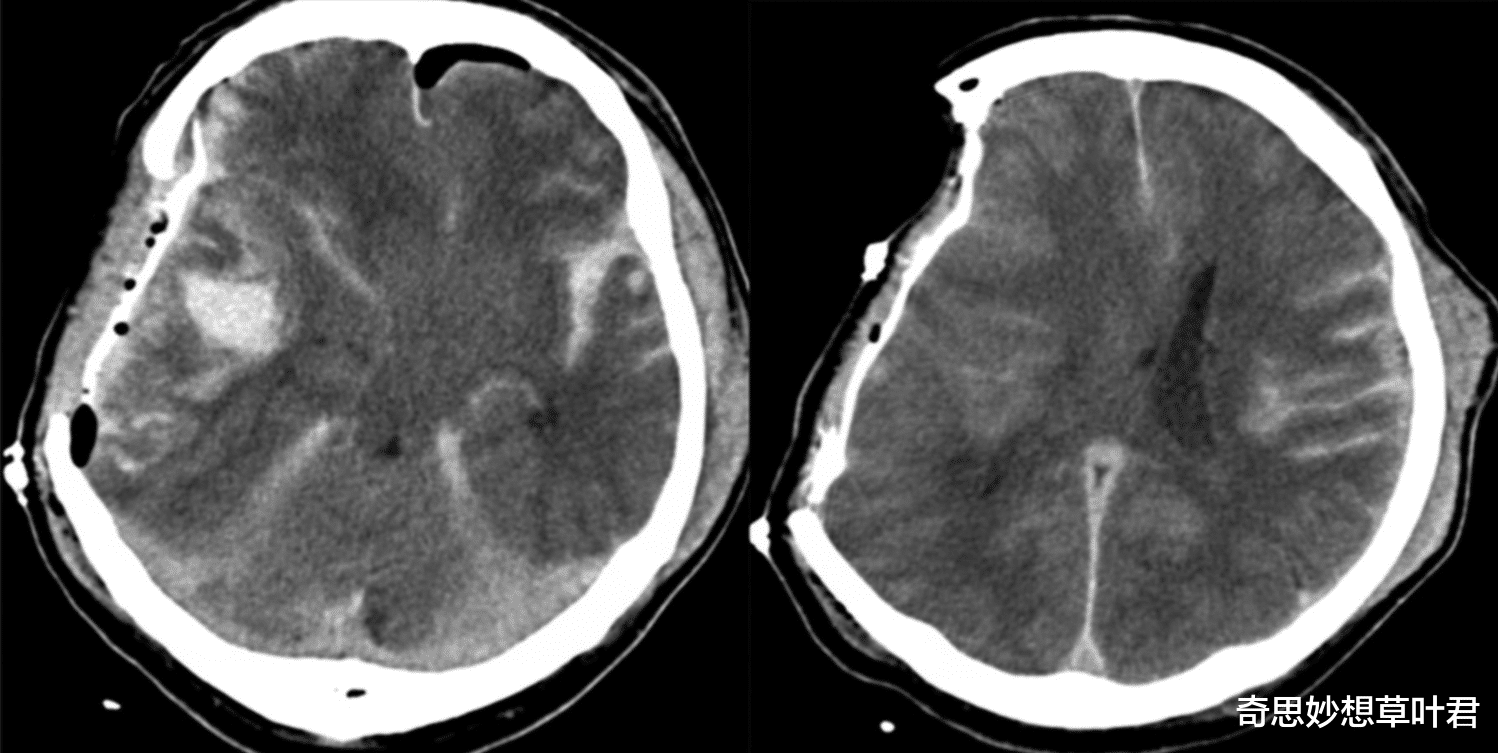

这时候医生决定给他做个脑部扫描 , 看看这个男子的脑部有没有异常 。 当扫描结果出来之后医生被震惊了 , 因为这个44岁的法国男子竟然没有脑子 。 从医多年来这位医生从来没有见过这样的脑部扫描图 , 这个男子本来应该是大脑的位置空空如也 。

不过吃惊归吃惊 , 这位医生仔细观察发现这名男子的脑子完全不同于正常人 , 他的大脑体积只有正常人的10% , 而其他部分完全消失不见 。

由于该案例确实罕见 , 医院随即调来了脑科专家会诊 , 然后经过进一步的研究发现:这个男子的头骨里充满了液体 , 外部只有一层薄薄的脑组织皮层 , 而大脑的内部几乎已经被液体完全占领 。 后来医生了解到 , 这个法国男子曾经在婴儿时期就出现过“脑积水” , 当时医院在他的脑子里放有治疗支架 , 定期向外排出多余的脑积水 。

不过这个支架在他14岁的时候就被取了出来 , 因为当时医院方面觉得这个男孩的情况已经稳定 , 可以取出支架了 。 然而这一取不要紧 , 30多年来这个男子大脑中的脑积水不断增多 , 然后一点一点地开始侵蚀他的大脑 , 等到现在被发现的时候 , 他的大脑部分已经被侵蚀掉了90% 。